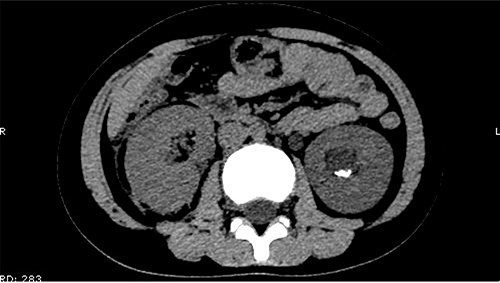

On 25 February, the patient complained of left back pain, nausea and vomiting. A further CT scan showed some irregular high-density shadows persisted in the left renal pelvis (Fig. 3) and an irregular high-density shadow was present in the left upper ureter (Fig. 4); furthermore, hydronephrosis was apparent in the left renal pelvis. There were no abnormalities in the bladder.

Some irregular high-density shadows persisted in the left renal pelvis, hydronephrosis was apparent in the left renal pelvis.